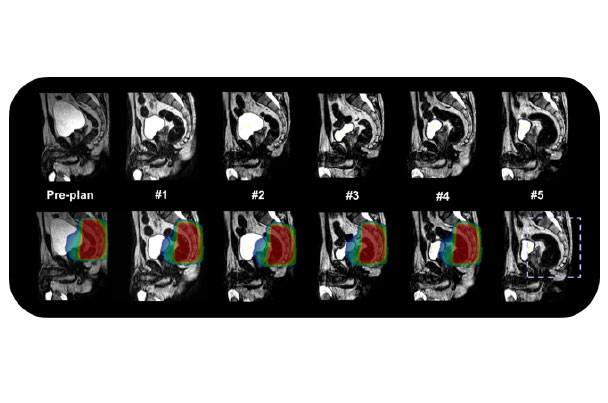

随着生活水平的提高,前列腺癌大发病逐渐上升,剂量学研究和初步的临床实践已经显示调强是当今放疗前列腺癌的最好照射技术,有广泛的应用前景,磁共振引导技术可以更好的对前列腺组织进行分辨,可以进行功能保留行治疗及肿瘤消融治疗,同时磁共振功能成像技术也为治疗疗效提供生物学依据。

磁共振实时成像可动态监测由于膀胱充盈不同或肠道蠕动带来的靶区位置形状改变,并进行自适应计划调整,更好的提高靶区剂量覆盖。